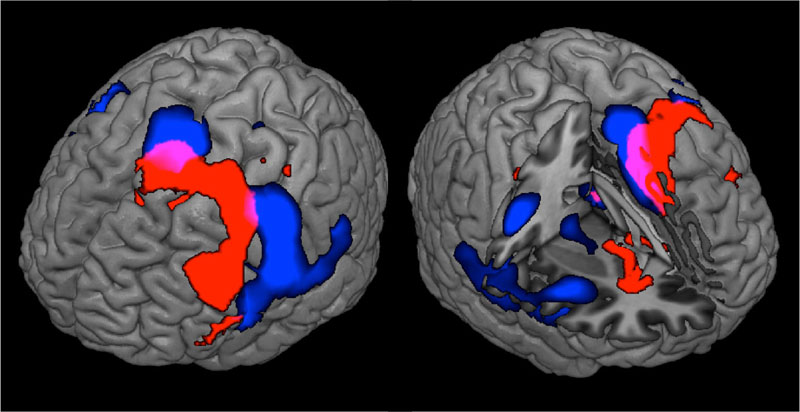

Нейрохирурги Пироговского Центра проводят апробацию первого русскоязычного протокола предоперационного картирования речи в клинической практике у пациентов с опухолями головного мозга и эпилепсией.

Отделению нейрохирургии Пироговского Центра исполнилось 8 лет. За это время его специалисты прооперировали около 10 тысяч пациентов. Ежегодное число операций за время работы отделения выросло с 400 до 2,5 тысяч в год. Здесь развивается несколько уникальных технологий и методов лечения пациентов с эпилепсией, опухолями головного мозга и дегенеративными заболеваниями позвоночника. Ежегодно около 400 пациентов с эпилепсией проходят предхирургическое обследование.

Пироговский Центр в сотрудничестве со Сколковским институтом науки и технологий, ООО «Сбермедии» и ООО «Иммерсмед» продолжил исследовать возможности применения цифровых инноваций в медицине. Ведутся проекты по использованию современных технологий, включая машинное обучение, для обработки результатов магнитно-резонансной томографии и электроэнцефалографии. Цель проекта — изучение причин и своевременная диагностика эпилепсии, что позволит не только приоткрыть тайны функциональных структур головного мозга, но и вовремя начать прием наиболее подходящих медикаментов, провести нейрохирургическую операцию, повысив тем самым вероятность полного излечения пациентов.

Внедрен современный протокол диагностики эпилептогенных очагов головного мозга — протокол SISCOM (Subtraction Ictal SPECT Co-Registered to MRI)